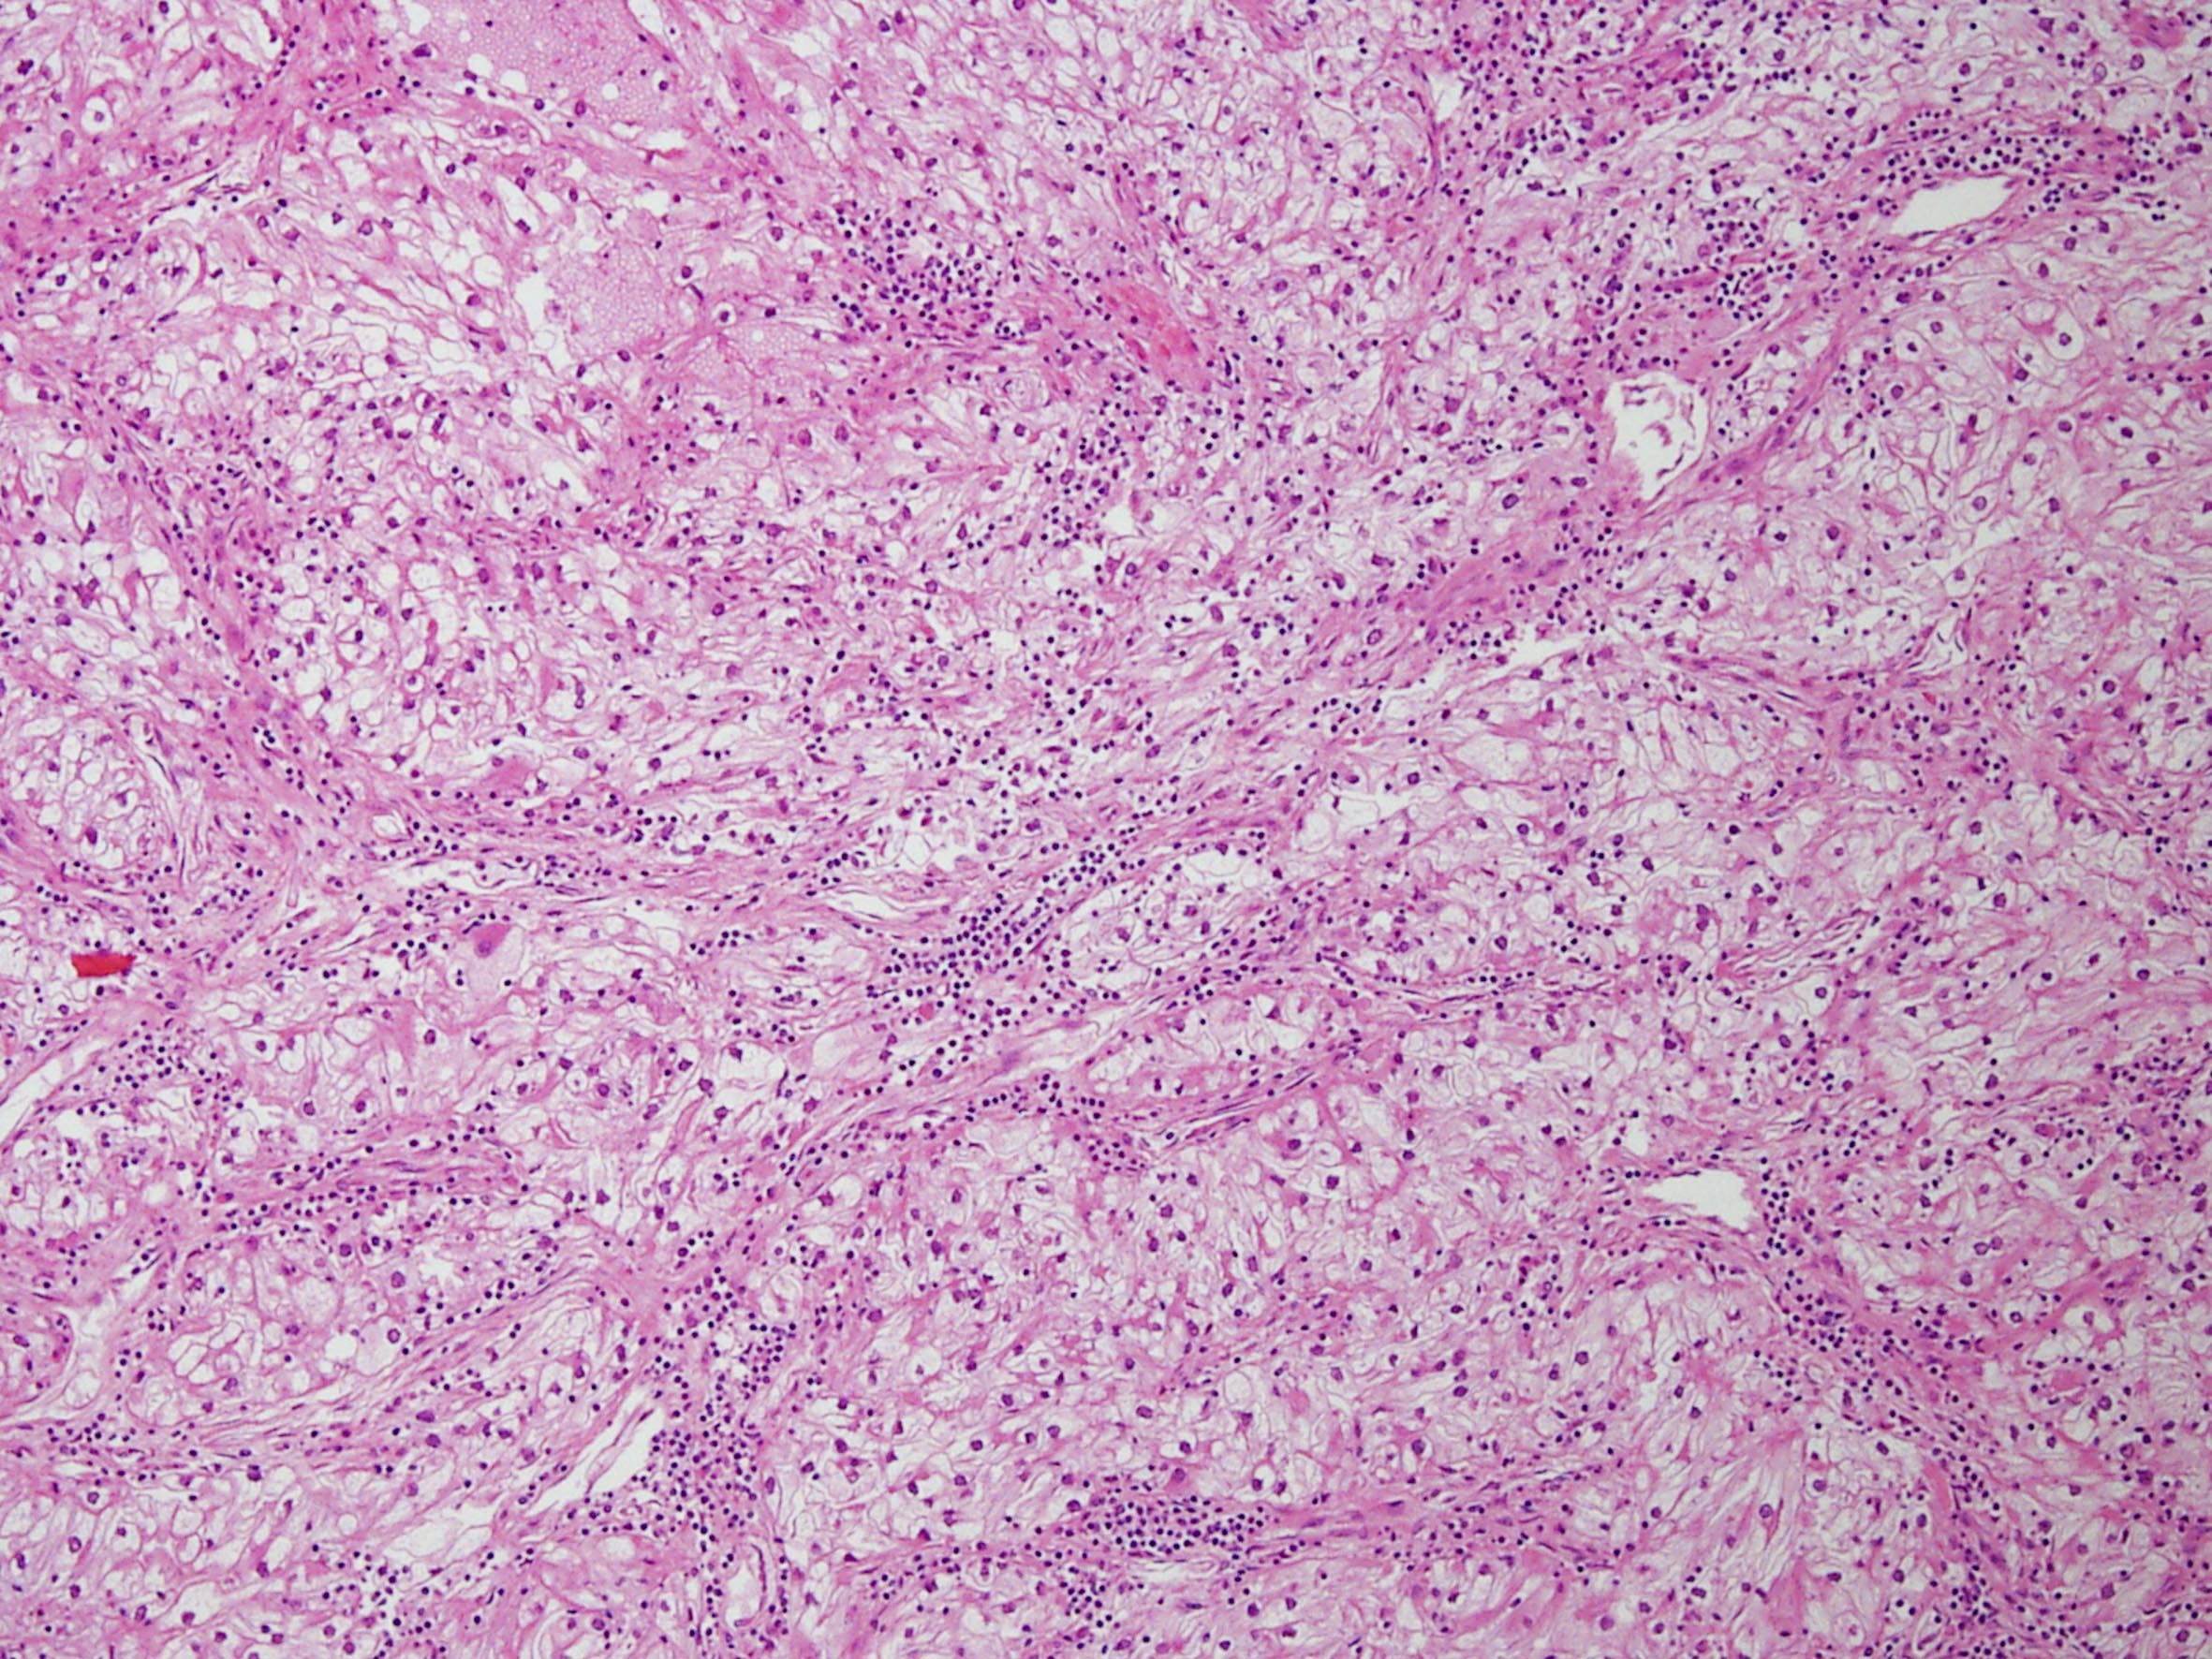

Classification of renal tumors

Case ID: 258